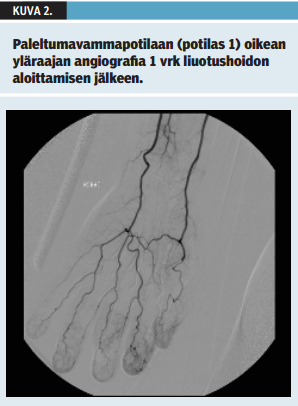

Potilas 1 on 49-vuotias päihdeongelmainen mies. Aikaisempina sairauksina hänellä on ollut mahalaukun ja ruokatorven tulehdus. Potilas löydettiin päihtyneenä lumihangesta makaamasta. Ensiavussa tärykalvosta mitattu ruumiinlämpö oli 31 °C. Ulkoisia vammoja potilaalla ei todettu. Potilasta lämmitettiin kehonulkoisin lämpöpeittein, ja kestokatetrin kautta mitattu lämpötila nousi nopeasti yli 35 °C:een. Kliinisessä tutkimuksessa kädet olivat kalpeat ja verenkierrottoman oloiset lämmityksen jälkeen. Kummastakaan kädestä ei saatu dopplerlaitteella mitattua valtimoverenkiertosignaalia rannetasolta tai sormista. Potilaalle tehtiin paleltumavammapotilaan protokollan (taulukko 1 «»1) mukaisesti yläraajojen verisuonten varjoainetutkimus (angiografia). Molempien yläraajojen värttinä- ja kyynärvaltimot täyttyivät erittäin hitaasti, eivätkä sormivaltimot eivät täyttyneet luotettavasti (kuva 1 «»2). Potilaalle annettiin protokollan (taulukko 2 «»3) mukainen valtimon sisäinen liuotushoito, jota jatkettiin kahden vuorokauden ajan. Lisäksi potilaalle aloitettiin asetyylisalisyylihappo- ja ibuprofeiinilääkitys. Vuorokauden kuluttua tehdyssä kontrollivarjoainekuvauksessa verenkierto oli parantunut (kuva 2 «»4). Liuotushoidon päättymisen jälkeen käsien verenkierto oli kliinisesti hyvä ja Allenin testillä arvioiden molempien rannevaltimoiden verenkierto oli normalisoitunut. Potilas kotiutui 5 vrk:n sairaalahoidon jälkeen. 6 viikon kuluttua paleltumavammasta potilaan käsissä oli vielä tunnon alentumaa ja kylmäherkkyyttä. Amputaatioita tai leikkaushoitoa ei tarvittu.